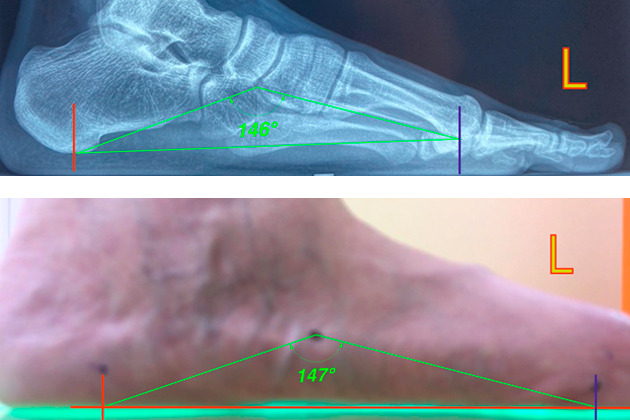

Диагностика стоп DPGtech - это система цифровой планотографии, гониометрии и моделирования цифрового слепка стопы.

1. С диагностической целью получать высококачественное изображение стопы и голени для расчёта гониометрических параметров комплекса подтаранного сустава и суставов предплюсны, определения угла стопы, а также выполнять плантографию.